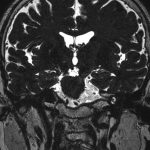

491

'23年12月

50代

頭蓋咽頭腫

頭蓋内腫瘍摘出術

No.’23_125 手術前1

No.’23_125 手術前2